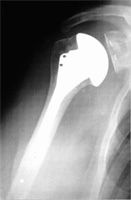

Dans un premier temps, on essaie le traitement médical associée à de la rééducation (il s’agit d’antalgiques et d’anti-inflammatoires non stéroïdiens). Quand ce traitement n’est plus efficace, on peut réaliser des infiltrations d’Altim. En cas d’échec des différents traitements, on envisagera une prothèse d’épaule. Une prothèse sert à remplacer la tête de l’humérus puisque le cartilage est usé. Elle peut également remplacer la glène de l’omoplate si celle-ci est usée. Plusieurs types de prothèses existent en fonction des causes de l’arthrose et le choix de la prothèse est fait avec le chirurgien.

Prothèse épaule |

Radio d’une prothèse à l’épaule |